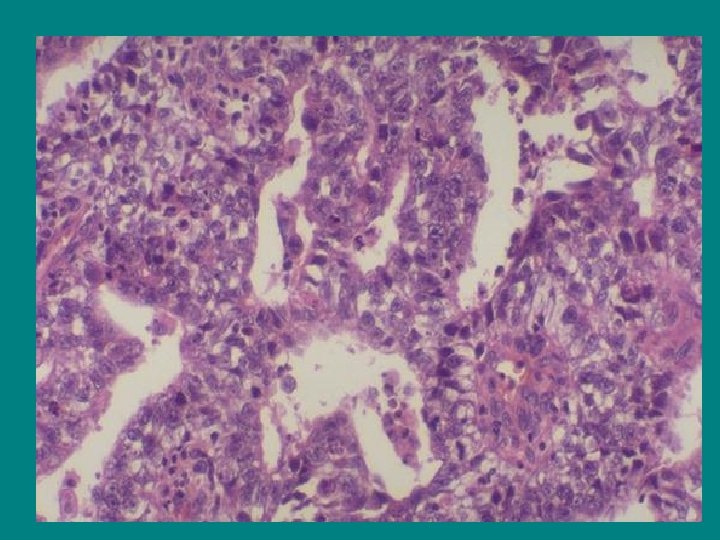

EMBRYONAL CANCER • Oftast som komponent i blandtumör • Cytostatikakänslig ; differentierar ut till moget teratom under behandling